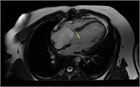

心室中隔欠損症(Ventricular Septal Defect, VSD)

1. 成人循環器内科医が診るVSDのほとんどは小欠損孔のrestrictive VSDとなる。なかにはsmall-moderate size(小~中欠損孔)restrictive VSDで小児期には血行動態的に影響がなかったが、成人期に心室コンプライアンス低下や体血管抵抗の上昇により左→右シャントが増加して左室拡大をきたすことがある。

1. 必要な検査と所見:身体所見、心エコー

1. 大動脈弁閉鎖不全症、肺高血圧合併例は専門施設への紹介を検討する。